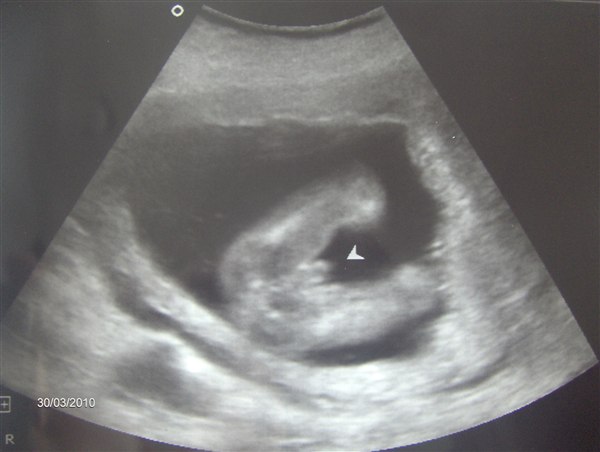

jeg har været til md scanning.. og damen var 95 % sikker på det er en pige jeg har derinde i maven..

sidder nu og tænker lidt på om der evt er nogen af jer der ligger inde med nogle alm 2d scanninger hvor man kan se kønnet.

Det første billede taler vist for sig selv..